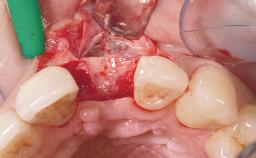

Early Placement of an Implant in a Maxillary Right Central Incisor Site

This 41-year-old female patient was referred to the clinic for the replacement of the right central incisor, since the tooth had developed a root fracture in the long axis that made extraction necessary. The healthy, non-smoking patient was first seen with the tooth still in place. A detailed Esthetic Risk Assessment was performed.The patient was worried about her dental esthetics and had high expectations for a successful treatment outcome from an esthetic point of view. The patient had a medium lip line that displayed parts of the gingiva in the anterior maxilla upon smile.